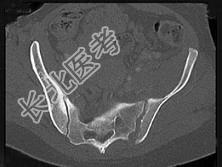

- 单项选择题男,56岁, 右髋部疼痛,结合图像, 最可能的诊断是 ( )

A、骶髂关节炎

B、骶髂关节结核

C、强直性脊柱炎

D、骨转移瘤

E、类风湿关节炎